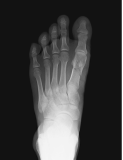

Metatarsal fracture

age 16

Femur fracture

age 13